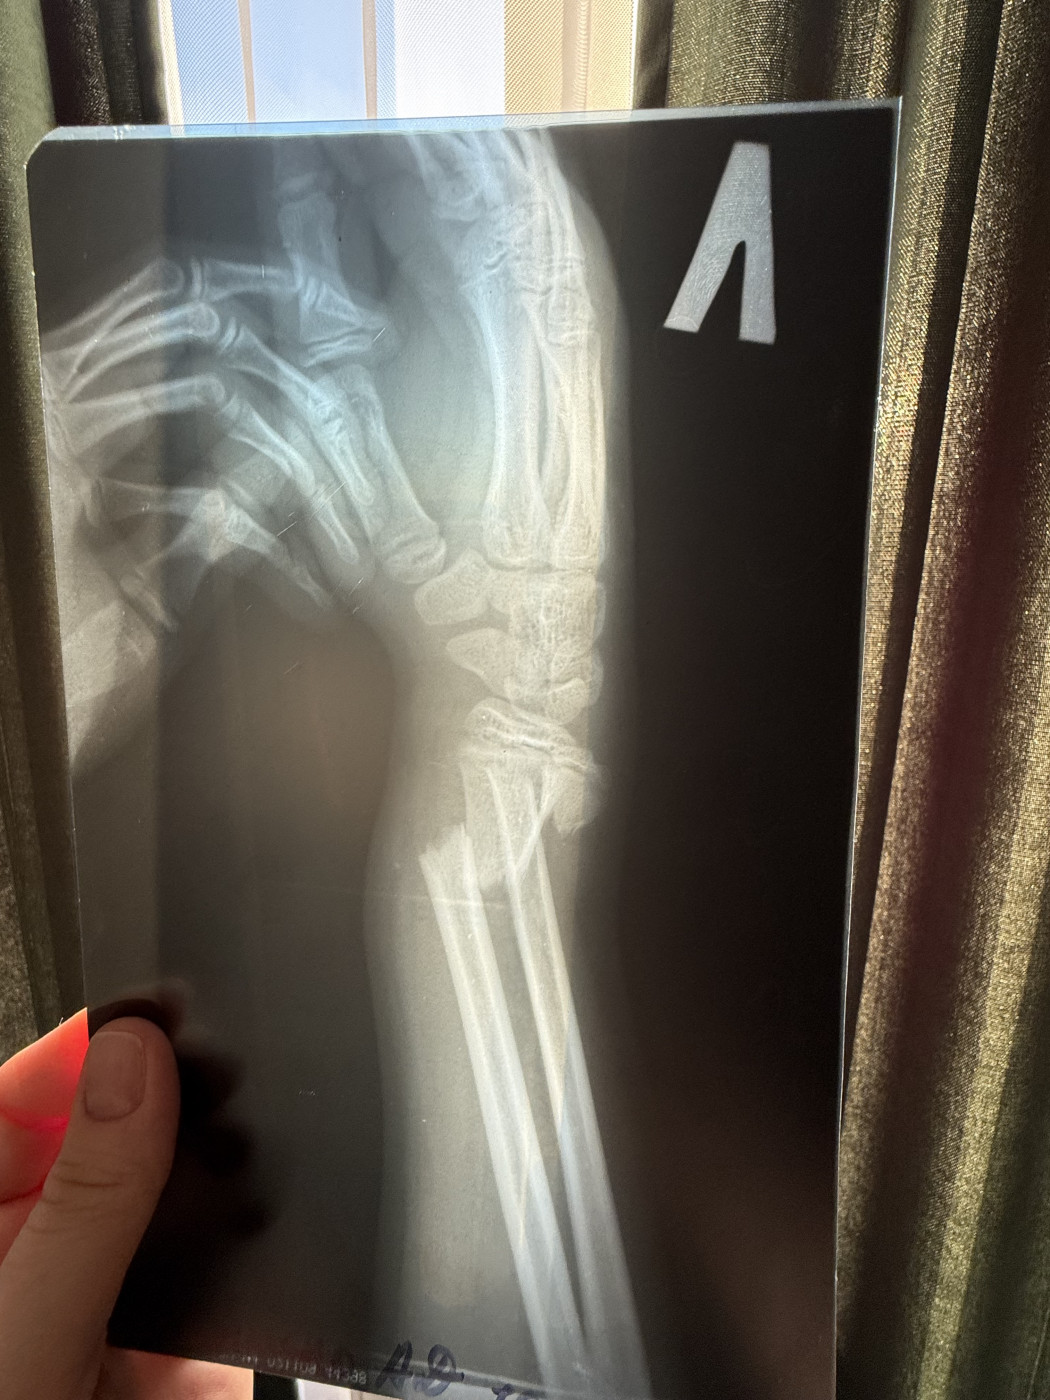

Перелом двух костей предплечья.   1 ответ

Здравствуйте. Прошу консультации у Вас знающие, уважаемые специалисты. Данный прелом относится к нижней трети (лучезапястный сустав, кисть) или к средней трети предплечья?